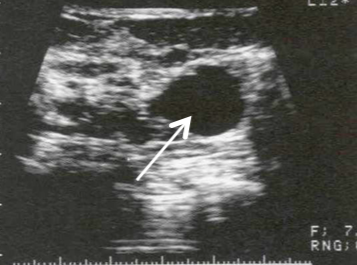

A woman presents with bloody nipple discharge, there is no palpable mass. US is performed

Intraductal papilloma